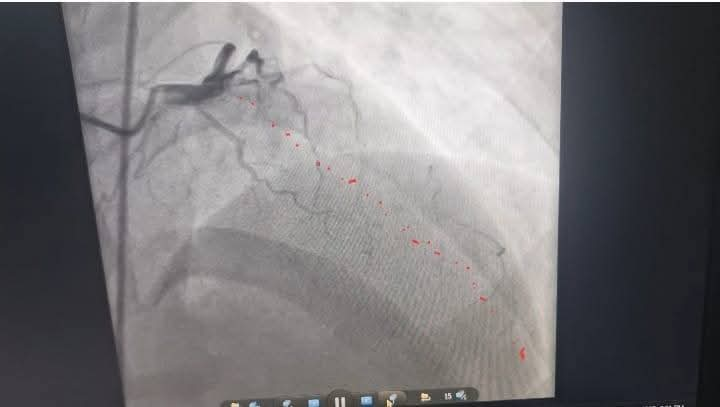

وأضاف "دويدار" أنه فور الانتهاء من فحص المريض تم العرض على الفريق الطبي بوحدة قسطرة القلب، الذي قرر على الفور إجراء قسطرة قلبية عاجلة لاستكشاف الشرايين التاجية للقلب، حيث تبين أن الشريان الأمامي الرئيسي كان مسدودًا بالكامل، وتم فتح الشريان وتركيب دعامة بنجاح تام، واستقرت حالة المريض بعد العملية ويستكمل علاجه بالمستشفى.